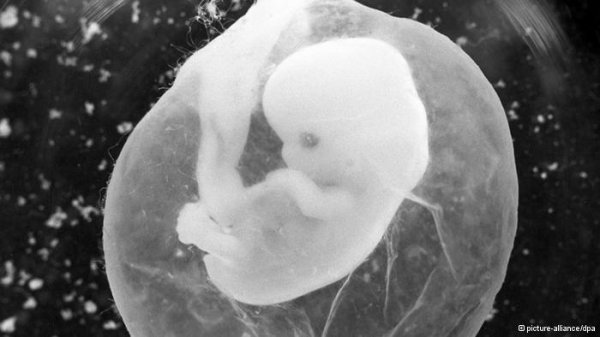

یافت جنین در بدن نوزادی در هند

پزشکان در هند در بدن نوزادی دو ماهه یک جنین یافتند. تورم شکم این نوزاد والدین او را به این امر آگاه کرد. پزشکان بههنگام عمل جراحی، پا، سر، مو و همچنین بافتهای مختلفی همچون سلولهای کلیه و ماهیچه پیدا کردند.